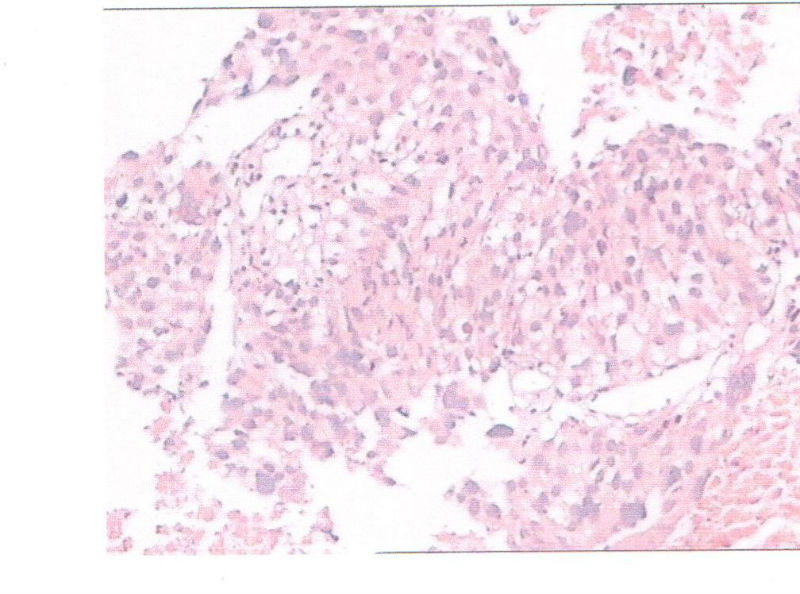

看看是鳞癌还是腺癌,或是小细胞癌?

病理诊断鳞癌

少量表浅的黏膜细胞异型性明显,极向紊乱,诊断原位鳞癌(未见粘膜下间质,不出外浸润癌的可能性)。

癌没有问题,复切一下,看有没有浸润

少量表浅的黏膜细胞异型性明显,极向紊乱,诊断原位鳞癌

分化差的非小细胞癌,首先考虑为鳞状细胞癌。应该重新制片染色。